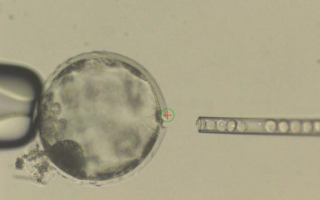

Cientistas descobrem forma de criar órgãos humanos em animais